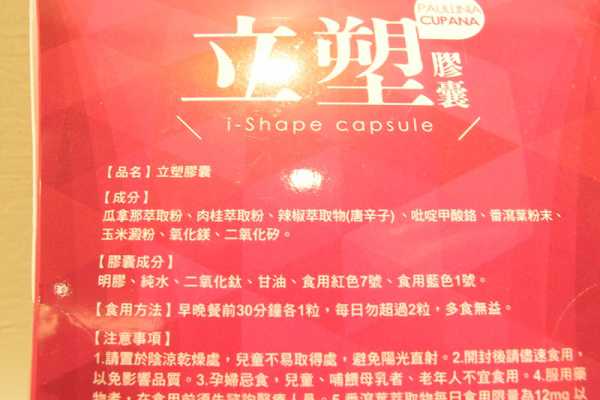

Supercut塑魔纖立塑膠囊的成分有:瓜拿那萃取粉、肉桂萃取粉、辣椒萃取物(唐辛子)、吡啶甲酸鉻、番瀉葉粉末、玉米澱粉、氧化鎂、二氧化矽。

之前上過相關課程,成分表是依照每項成分的多寡來排列順序,排在最前面的就是產品的主要成分!

食用方式:早晚餐前30分鐘各1粒,每日不超過2粒。(多食無益)

番瀉葉萃取物每日食用限量為12mg以下,